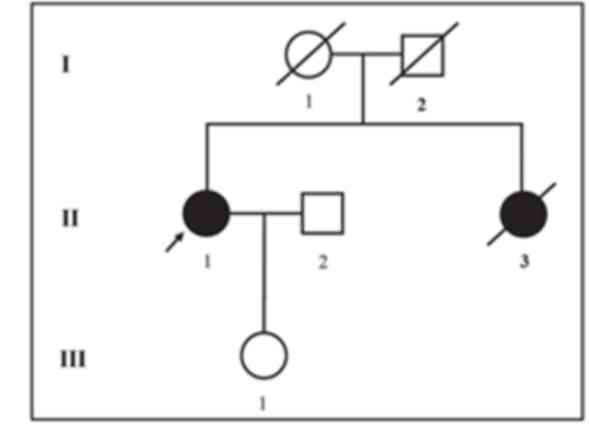

The proband investigated in the current study is a

54-year-old Chinese female clinically diagnosed with ovarian cancer

who belongs to a non-consanguineous Chinese family. The proband's

elder sister passed away at the age of 46 years as a result of

ovarian cancer. The age and cause of mortality for the proband's

parents are unknown (Fig. 1). The

Since the proband's elder sister passed away at an

age of 46 years due to ovarian cancer, it can be hypothesized that

she carried the same mutation in BRCA2. In addition, the

proband's father or mother may carry the same mutation. However, as

the proband's elder sister and parents had passed away, it was not

possible to investigate this. The proband's children did not

volunteer genetic testing. Therefore, only the following

suggestions can be made. Firstly, it could be hypothesized that the

proband and her sister carried the same mutation on the

BRCA2 gene, which was inherited from their father or mother.

By contrast, it could be hypothesized that the mutation carried by

the proband is a de novo mutation. In this case, her parents

and sister would not have carried the same mutation. With the

knowledge that the proband's sister passed away due to ovarian

cancer, we speculate that the first hypothesis is more likely. The